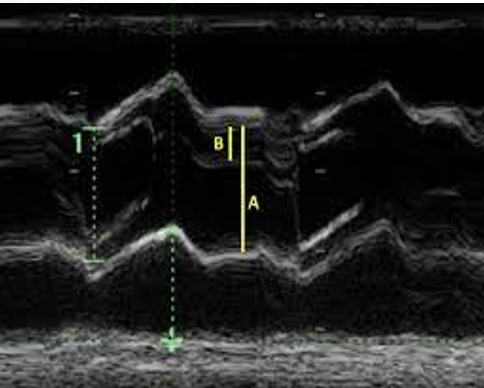

what does bicuspid ao valve appear like on m mode? **

eccentric line closure